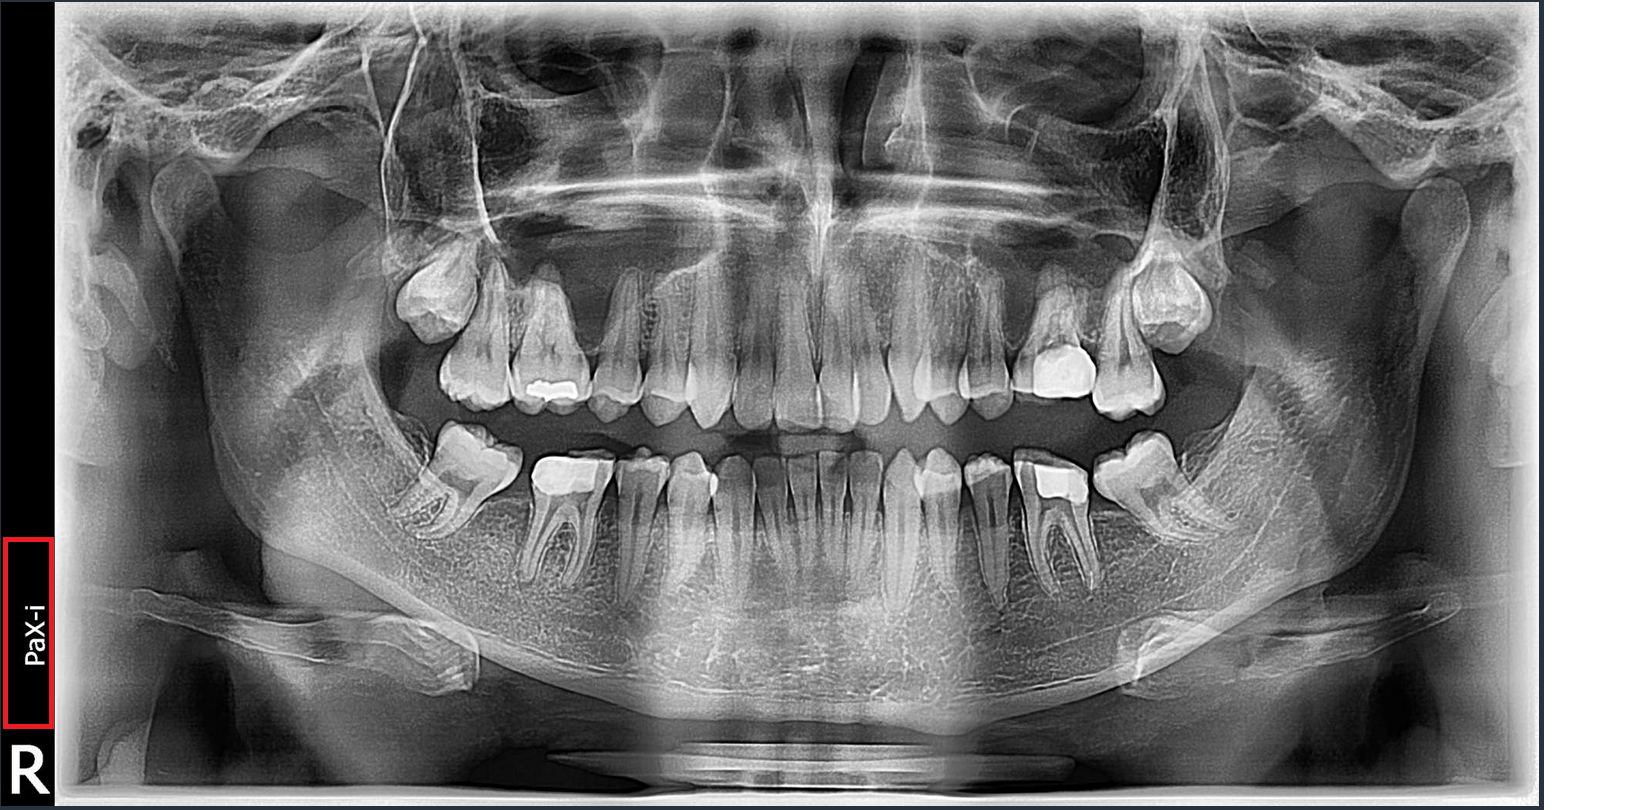

If you would like to add the Clinic or Dr. name to the Panoramic Marker information (inidcated in read below) this can be done by replacing the Manufacture information marker with the Clinic / Dr. name.